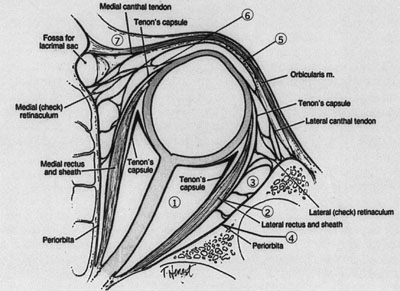

Fig. 6. Lateral orbitotomy through upper eyelid skin crease A. Photo demonstrating right globe ptosis present for more than 2 years. B. Axial CT scan showing a well outlined oval lesion in the lacrimal gland

fossa. C. Coronal CT showing lesion pushing globe inferiorly. D. Skin crease excision marked for lateral orbitotomy. E. Lateral orbital rim exposed. Bone cuts made above frontozygomatic suture

and at zygomatic arch. F. Lateral wall removed. Subperiosteal space exposed. Hard tumor could be

palpated in area of lacrimal gland. G. Benign mixed tumor of lacrimal gland removed. H. Bone sutured into place. I. Skin crease closed. |